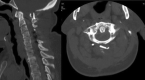

Successful arthrodesis at the craniocervical junction and atlantoaxial joint can be more challenging than in other segments of the cervical spine. Different techniques for spinal fixation in this region have been well described, along with auxiliary methods to improve fusion rates. The occipital vascularized bone graft is a novel technique that can be used to augment bony arthrodesis in the supra-axial cervical spine. It provides the benefits of a vascularized autologous graft, such as accelerated healing, earlier fusion, and increased strength. This technique can be learned with relative ease and may be particularly helpful in cases with high risk of nonunion or pseudoarthrosis in the upper cervical spine.